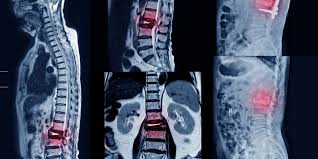

Los AINE y la teriparatida pueden ser las opciones de tratamiento preferidas para el tratamiento del dolor agudo en las fracturas vertebrales por compresión osteoporóticas. Aunque la calcitonina también demostró ser beneficiosa, su perfil de seguridad y los posibles efectos adversos restringen su aplicación generalizada. La evidencia limitada sobre los aparatos ortopédicos y los analgésicos subraya la necesidad urgente de investigaciones futuras. JAMA Netw Open. 3 de septiembre de 2024

La evidencia disponible no apoya el uso de muchas señales de alerta para descartar específicamente fracturas vertebrales en pacientes con dolor lumbar (DL). Sobre la base de la evidencia de estudios individuales, pocas señales de alerta individuales parecen informativas debido a que la mayoría tienen una exactitud diagnóstica deficiente según lo indican los cálculos imprecisos de los cocientes de probabilidad. Cuando se usaron combinaciones de señales de alerta el rendimiento pareció mejorar. Cochrane Database Syst Rev. 28 de noviembre de 2023